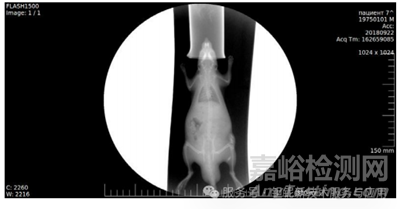

納米顆粒實(shí)驗(yàn): 稀土TaO?微粉制備納米顆粒(粒徑約 20 nm,圖 16),5% 混懸液皮下 / 肌內(nèi)注射大鼠,觀察 8 天內(nèi)的局部對(duì)比度與組織反應(yīng)(圖 17 - 圖 21)。

大鼠皮下注射實(shí)驗(yàn)顯示,5%納米混懸液在45分鐘內(nèi)形成清晰不透射線區(qū)域,8 天后仍可檢測到顆粒沉積,且無紅腫、纖維化等炎癥反應(yīng)(圖18-圖21)。

圖19.皮下給藥后8天的登記。

圖21.給藥后8天的登記。